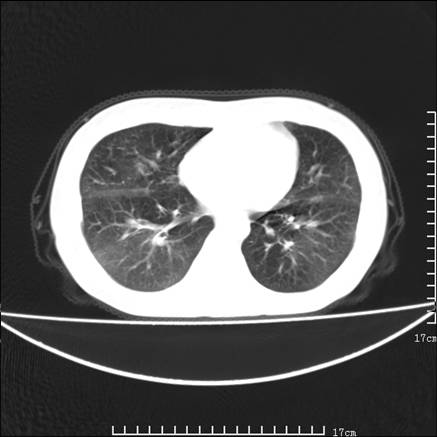

女,46岁,患胃溃疡多年,溃疡大小约1.0cm左右,后于5年前手术,病理为胃癌。主诉:半月前感冒后胸闷,气短,有咳嗽,无明显咳痰,无发热。偶有腰背部不适。

以下为高分辨扫描图像

双肺散在的 磨玻璃样及片状渗出性病灶,界限模糊。考虑:双肺感染!

双肺小叶间增厚,双肺散布粟米影和磨玻璃状影,以双肺上叶为重。结合病史考虑转移(癌性淋巴细管炎)可能性大。